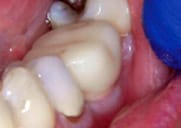

Figure 2

Tooth prep prior

to placement of Protemp™ Crown Temporization Material, buccal

view. |